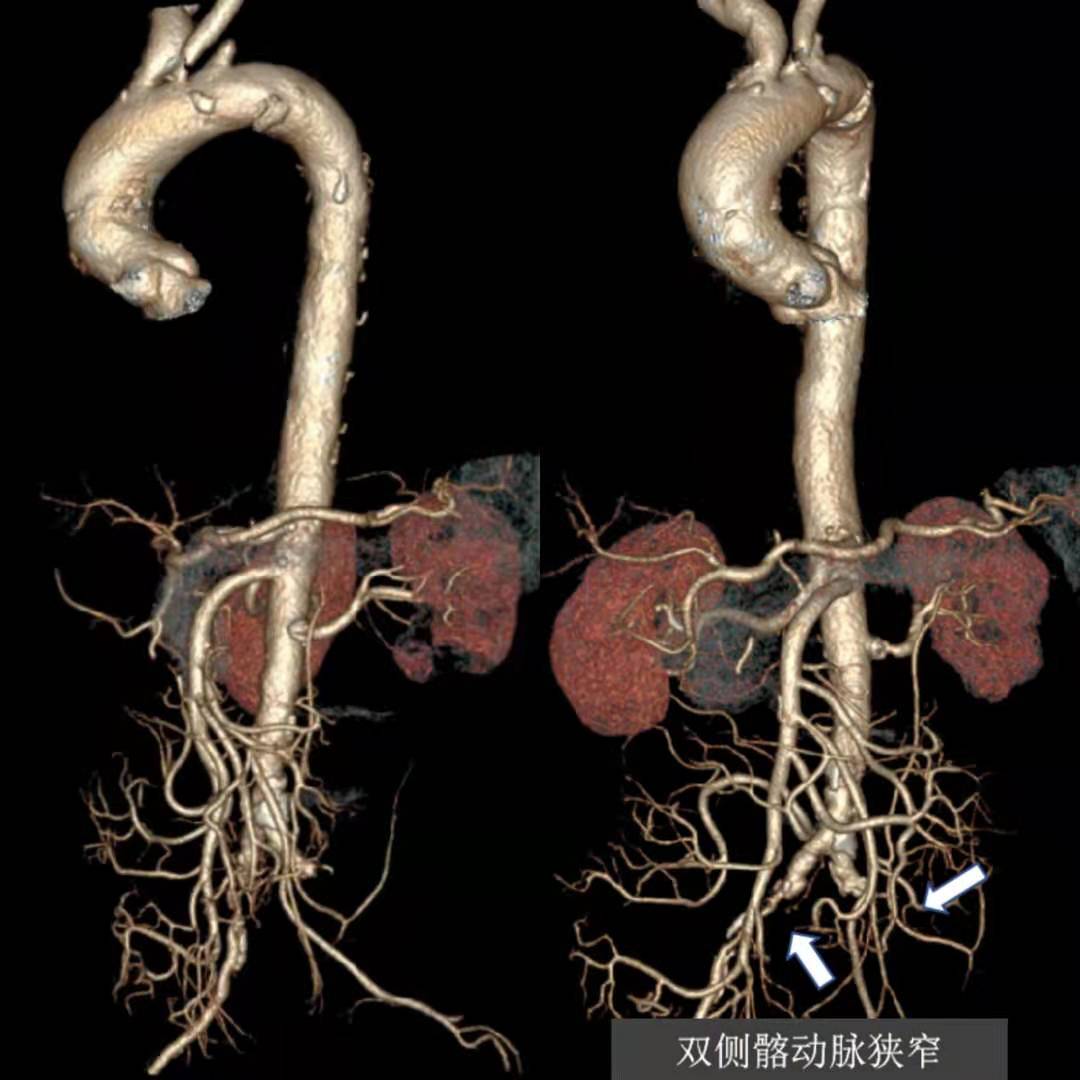

张大爷前不久,因为胸痛至苏州市独墅湖医院(苏州大学附属独墅湖医院)就诊行冠脉疾病治疗,住院期间完善CT血管检查,一查发现他的血管病变不得了。有主动脉弓穿透性溃疡、左侧锁骨下动脉起始段、双侧髂动脉闭塞(左侧重);张大爷诉说自己多年头晕不适、左下肢乏力,去多家医院检查左右上肢血压不一致,相差约40mmhg,左腕部也摸不到血管跳动。但自己一直没有重视,并且张大爷是个“老烟枪”,每天一包多,有糖尿病及高血压病史多年,没想到自己这么多血管出现了问题。

为此,张大爷找到独墅湖医院介入与血管外科张喜成主任,医生们根据影像,认为主动脉弓部穿透性溃疡最危险,很容易导致夹层或破裂引起生命危险,另外左锁骨下动脉、髂动脉均完全闭塞,这些都给治疗上带来挑战。经研究讨论后医生们决定同期解决多处血管问题。手术在我院先进的复合手术室进行,张主任、黄献琛博士和顾铖涛医师密切配合,术中因锁骨下动脉闭塞段的钙化很严重,很难开通,但他们艺高胆大,采用双向穿刺技术成功开通血管,然后用覆膜支架覆盖主动脉的溃疡,但由于溃疡距离左锁骨下动脉较近,故他们采用“浮潜”技术,既盖住了溃疡又保证分支血管的畅通。最后他们又成功开通了闭塞的左髂动脉,并植入血管支架解除了狭窄。